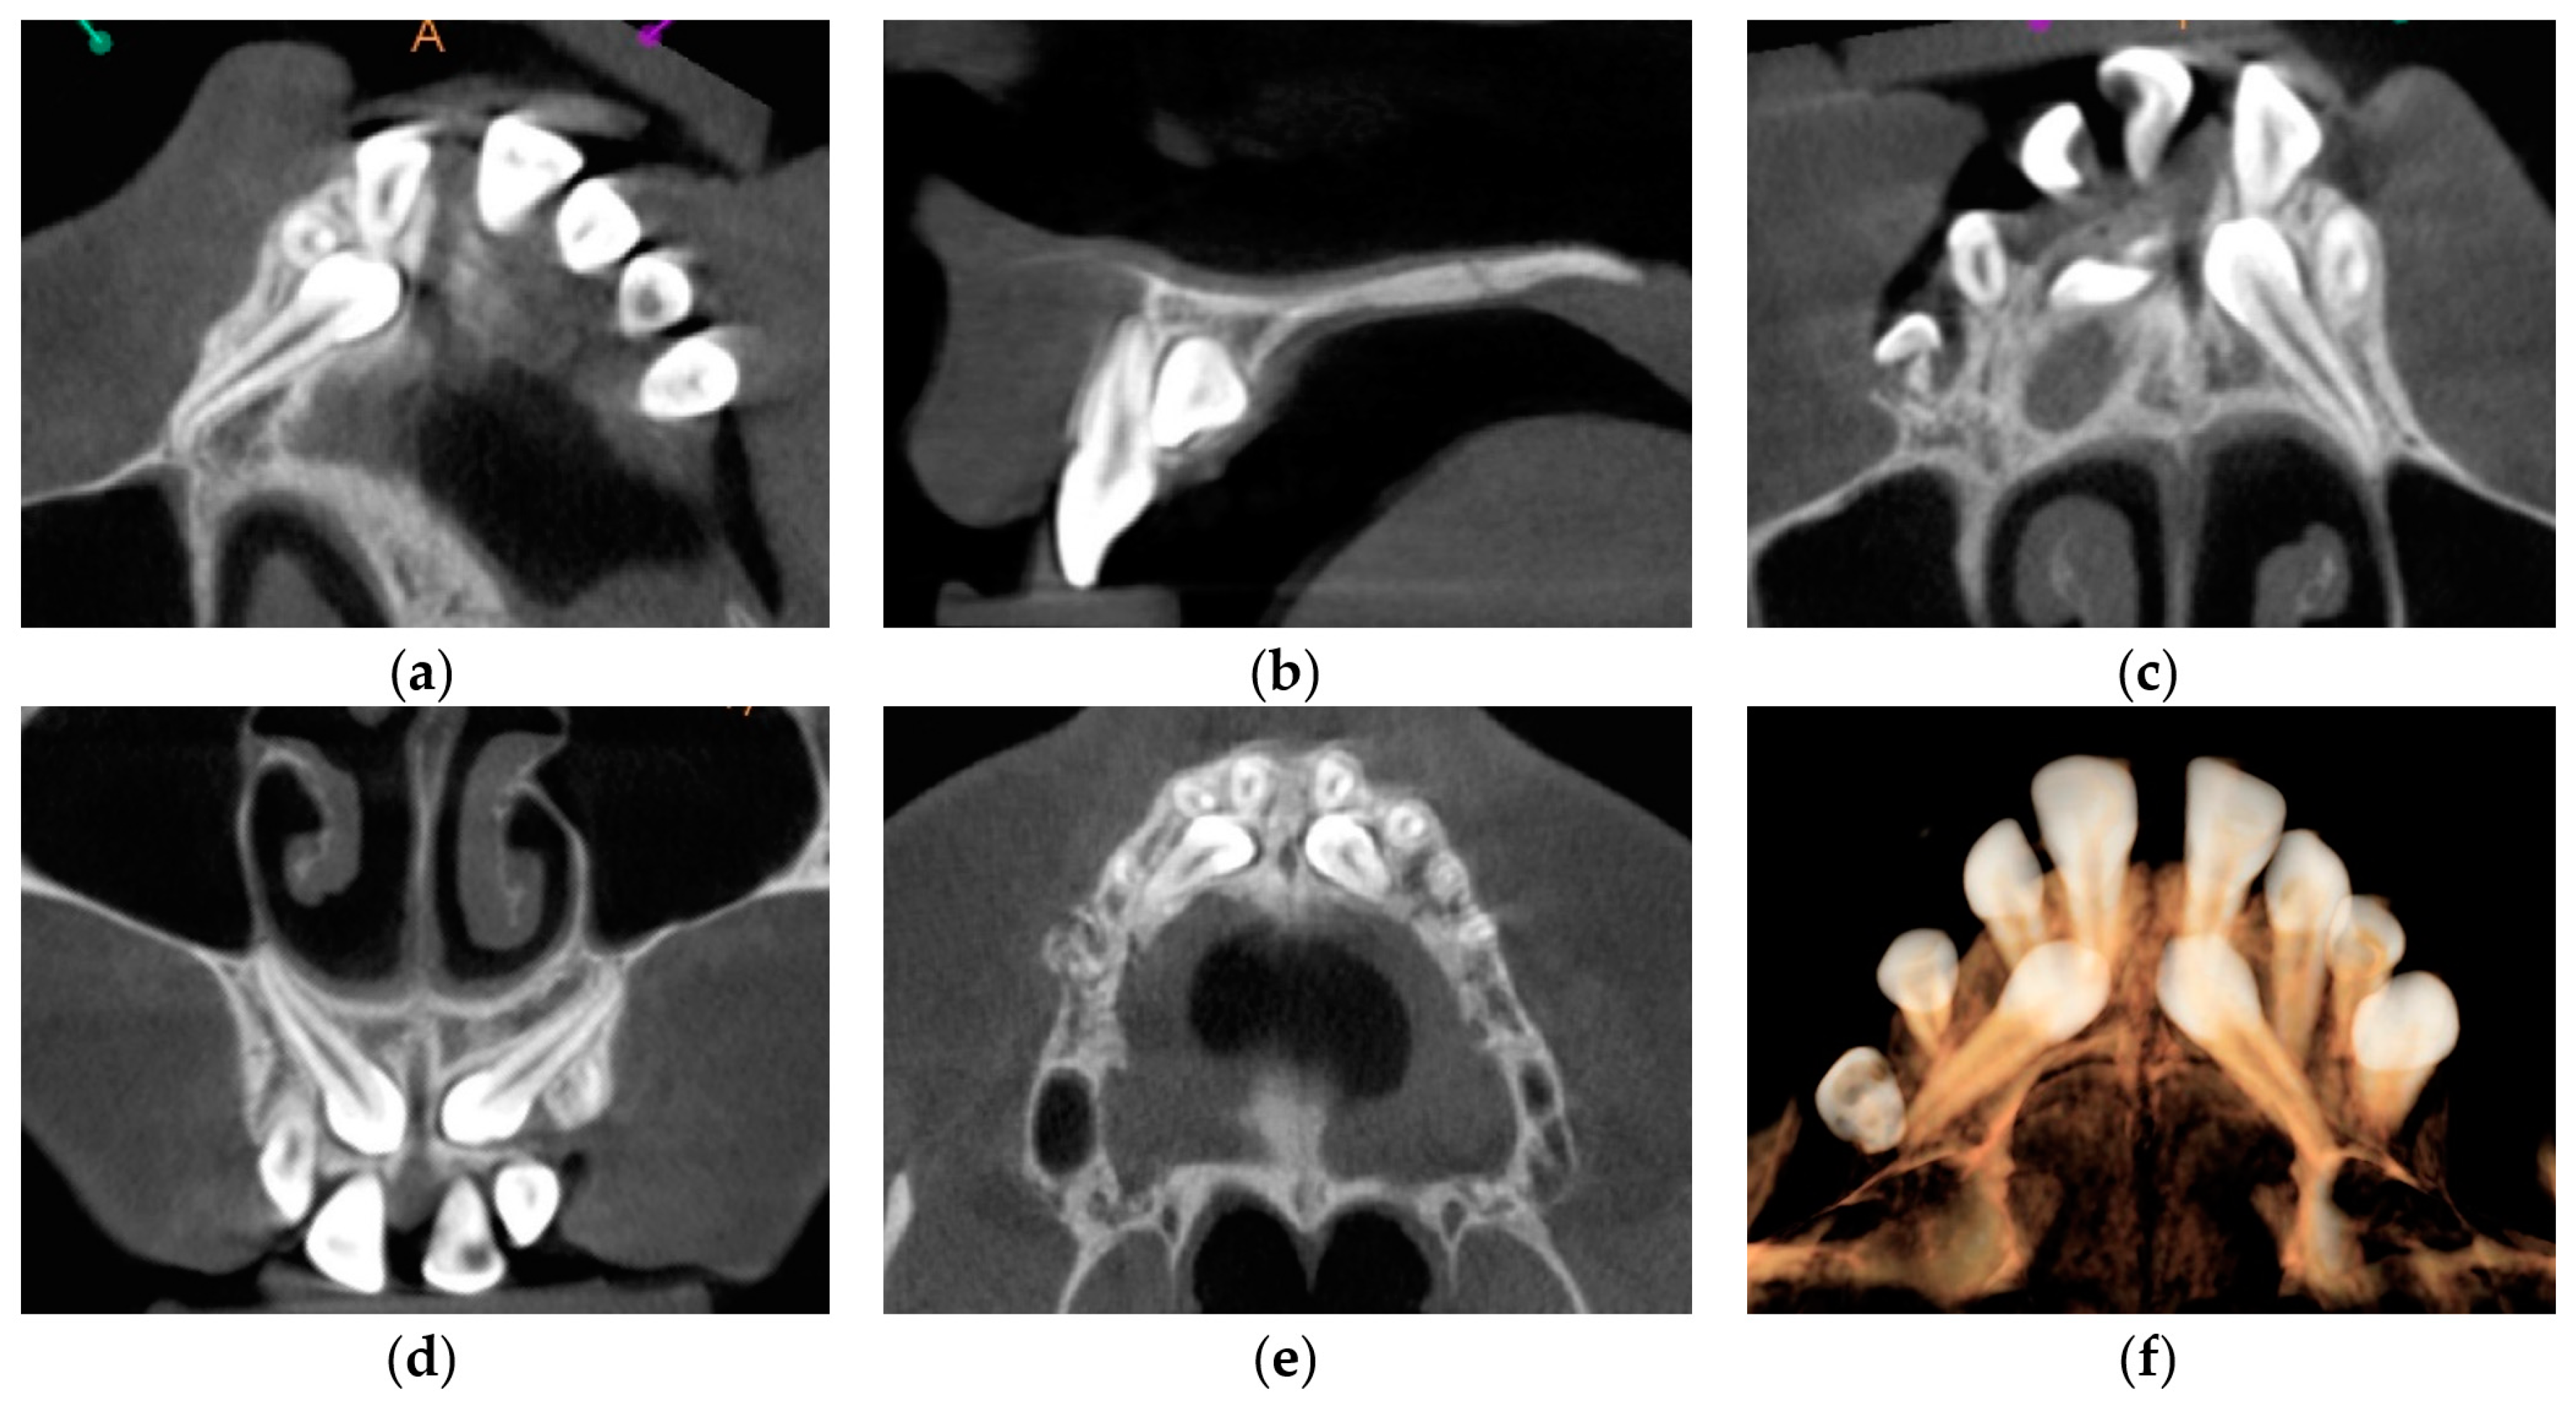

| October 2017 | PDCs’ surgical exposure—open technique; brackets bonded on PDCs; MIs tomas®-pin SD 06 (Dentaurum, Ispringen, Germany) inserted in the palatal alveolar region; 0.016″ × 0.022″ TMA cantilevers activated in distal and downward direction (50 g) (Figure 6a,b). |

| November 2017 | Visible orthodontic movement—exclusion of primary ankylosis (Figure 6c). |

| December 2017 | Increased mobility and tenderness of PDCs, dismantlement of cantilevers, button on the buccal side of UL3 (derotation), power chains to move the teeth (Figure 6d). |

| January 2018 | Teeth stability improved; 0.017″ × 0.025″ TMA cantilever with activation in downward and buccal directions for UR3, power chain for distal movement and derotation of UL3. |

| February 2018 | Button on the buccal side of UR3 (derotation), power chains for distal movements and derotations (Figure 6e). |

| April 2018 | Extraction of the upper right deciduous canine due to the collision with movement of UR3; 0.017″ × 0.025″ TMA cantilever activated for buccal movement of UR3 (50 g) (Figure 6f). |

| June 2018 | Partial fixed upper SS appliance Equilibrium® 2 0.022″ in Roth prescription (Dentaurum, Ispringen, Germany), 0.016″ NiTi wire, continuous metal ligature to create space for UL3; cantilever activation (Figure 6g). |

| August 2018 | Bracket on tooth no. 24; 0.016″ NiTi wire and open coil spring to create space for UL3; extraction of the upper left deciduous canine. |

| October 2018 | New MI tomas®-pin SD 08 (Dentaurum, Ispringen, Germany) was inserted in the buccal surface of left alveolar ridge; 0.017″ × 0.025″ TMA cantilever for buccal movement of UL3 (50 g) (Figure 6h). |

| November 2018 | Mobility of the buccal alveolar MI, the miniscrew was tightened and left to stabilize for a month; tooth no. 55 was extracted due to progressive reinclusion. |

| December 2018 | Buccal alveolar MI was lost and new MI tomas®-pin SD 10 (Dentaurum, Ispringen, Germany) was placed in the IZC; 0.017″ × 0.025″ TMA cantilever with buccal activation for UL3 (50 g). |

| February 2019 | Inflammation and submucous abscess in the IZC; MI removal; antibiotic. |

| April 2019 | New MI tomas®-pin SD 10 (Dentaurum, Ispringen, Germany) was inserted in the palatal suture and used as a direct anchorage with 0.017″ × 0.025″ SS cantilever and power chain for buccal movement of UL3 (50 g); 0.016” SS wire and bend-out for UR3 (Figure 6i). |

| May 2019 | Overcorrection of UR3 transversal relationship, 0.018″ SS wire and bend-out for tooth no. 22, new power chain from cantilever to UL3 for its buccal movement. |

| July 2019 | Tooth no. 22 in correct sagittal relationship; MI in the palatal suture used as an indirect anchorage: 0.017″ × 0.025 SS connection wire with tooth no. 24, 0.017″ × 0.025″ cantilever with buccal activation for UL3 (50g); 0.017″ × 0.025″ Cooper NiTi wire (Figure 6j,k). |

| March 2020 | The correct position of UL3; tooth no. 24 showed significant mobility; control panoramic X-ray: root resorption of tooth no. 24 (Figure 7); no possibility to conduct control visits on a regular basis due to COVID-19 pandemic—next appointment took place in November 2020. |

| November 2020 | 0.019″ × 0.025″ SS wire, torque expression, closure of spaces with power chain. |

| March 2021 | Removal of MIs, 0.021″ × 0.025″ TMA wire for torque expression in the upper arch; Fixed lower SS appliance Dentaurum Equilibrium® 2 0.022″ in Roth prescription (Dentaurum, Ispringen, Germany); 0.016″ NiTi wire; elastics 4 ½ oz. from palatal buttons on teeth no. 12 and 22 to the lower arch to correct the anterior crossbite (Figure 6l). |

| April–June 2021 | Further alignment of the lower teeth by means 0.017″ × 0.025″ NiTi, and next 0.019″ × 0.025″ SS; intermaxillary elastics 4 ½ oz and offset bends on teeth no. 12 and 22 were used to correct the anterior crossbite; elastic power chains for space closure. |

| August 2021 | Open sinus lift surgery with porcine bone-derived grafting material (The Graft™ bone substitute cancellous granules (Purgo Biologics, Seongnam, Republic of Korea) and BioCover™ resorbable collagen membrane (Purgo Biologics, Seongnam, Republic of Korea)) was performed on the right side of the maxilla. |

| March 2022 | Two dental implants were placed: tooth no. 14—Axiom® PX 3.4 × 12 mm (Anthogyr, Sallanches, France), tooth no. 15—Axiom® PX 3.4 × 10 mm (Anthogyr, Sallanches, France). |

| May–August 2022 | Finishing; control panoramic X-ray (Figure 8); 1st canine relationships and midline consistency; debonding of the brackets; fixed upper and lower retainers’ placement (0.027″ × 0.011″ 8-strand braided SS), tooth no. 24 was not fixed to the retainer due to increased mobility. |